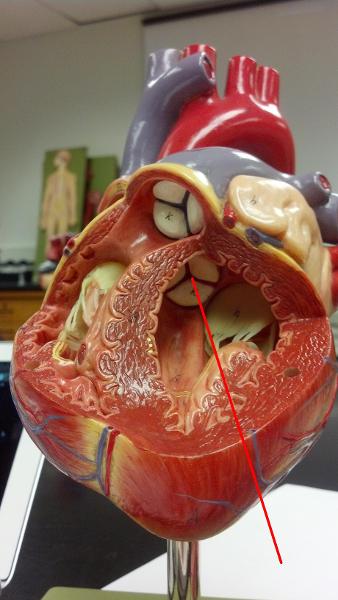

Chordae tendineae

Papillary muscles

Pectinate muscles